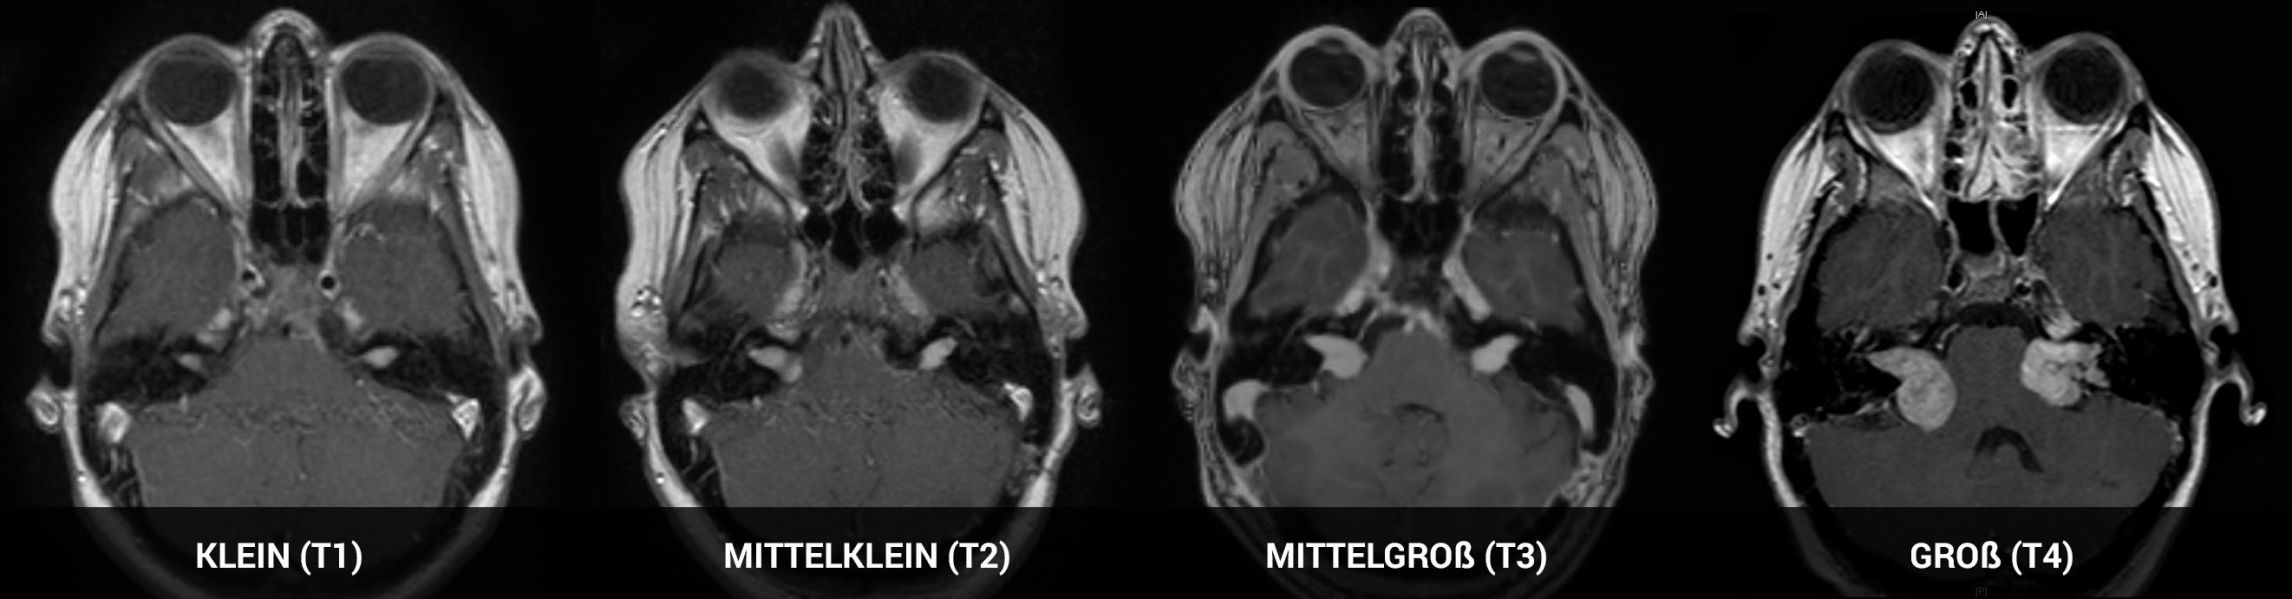

Größeneinteilung bei beidseitigen Vestibularisschwannomen anhand der Hannover-Klassifikation

Selbstverständlich gibt es hier starke Unterschiede im Größen- und Wachstumsverhalten und einige Varianten sind aus der Grafik zu entnehmen. Die Größeneinteilung wird anhand der Hannover-Klassifikation vorgenommen von klein (T1) bis sehr groß (T4).